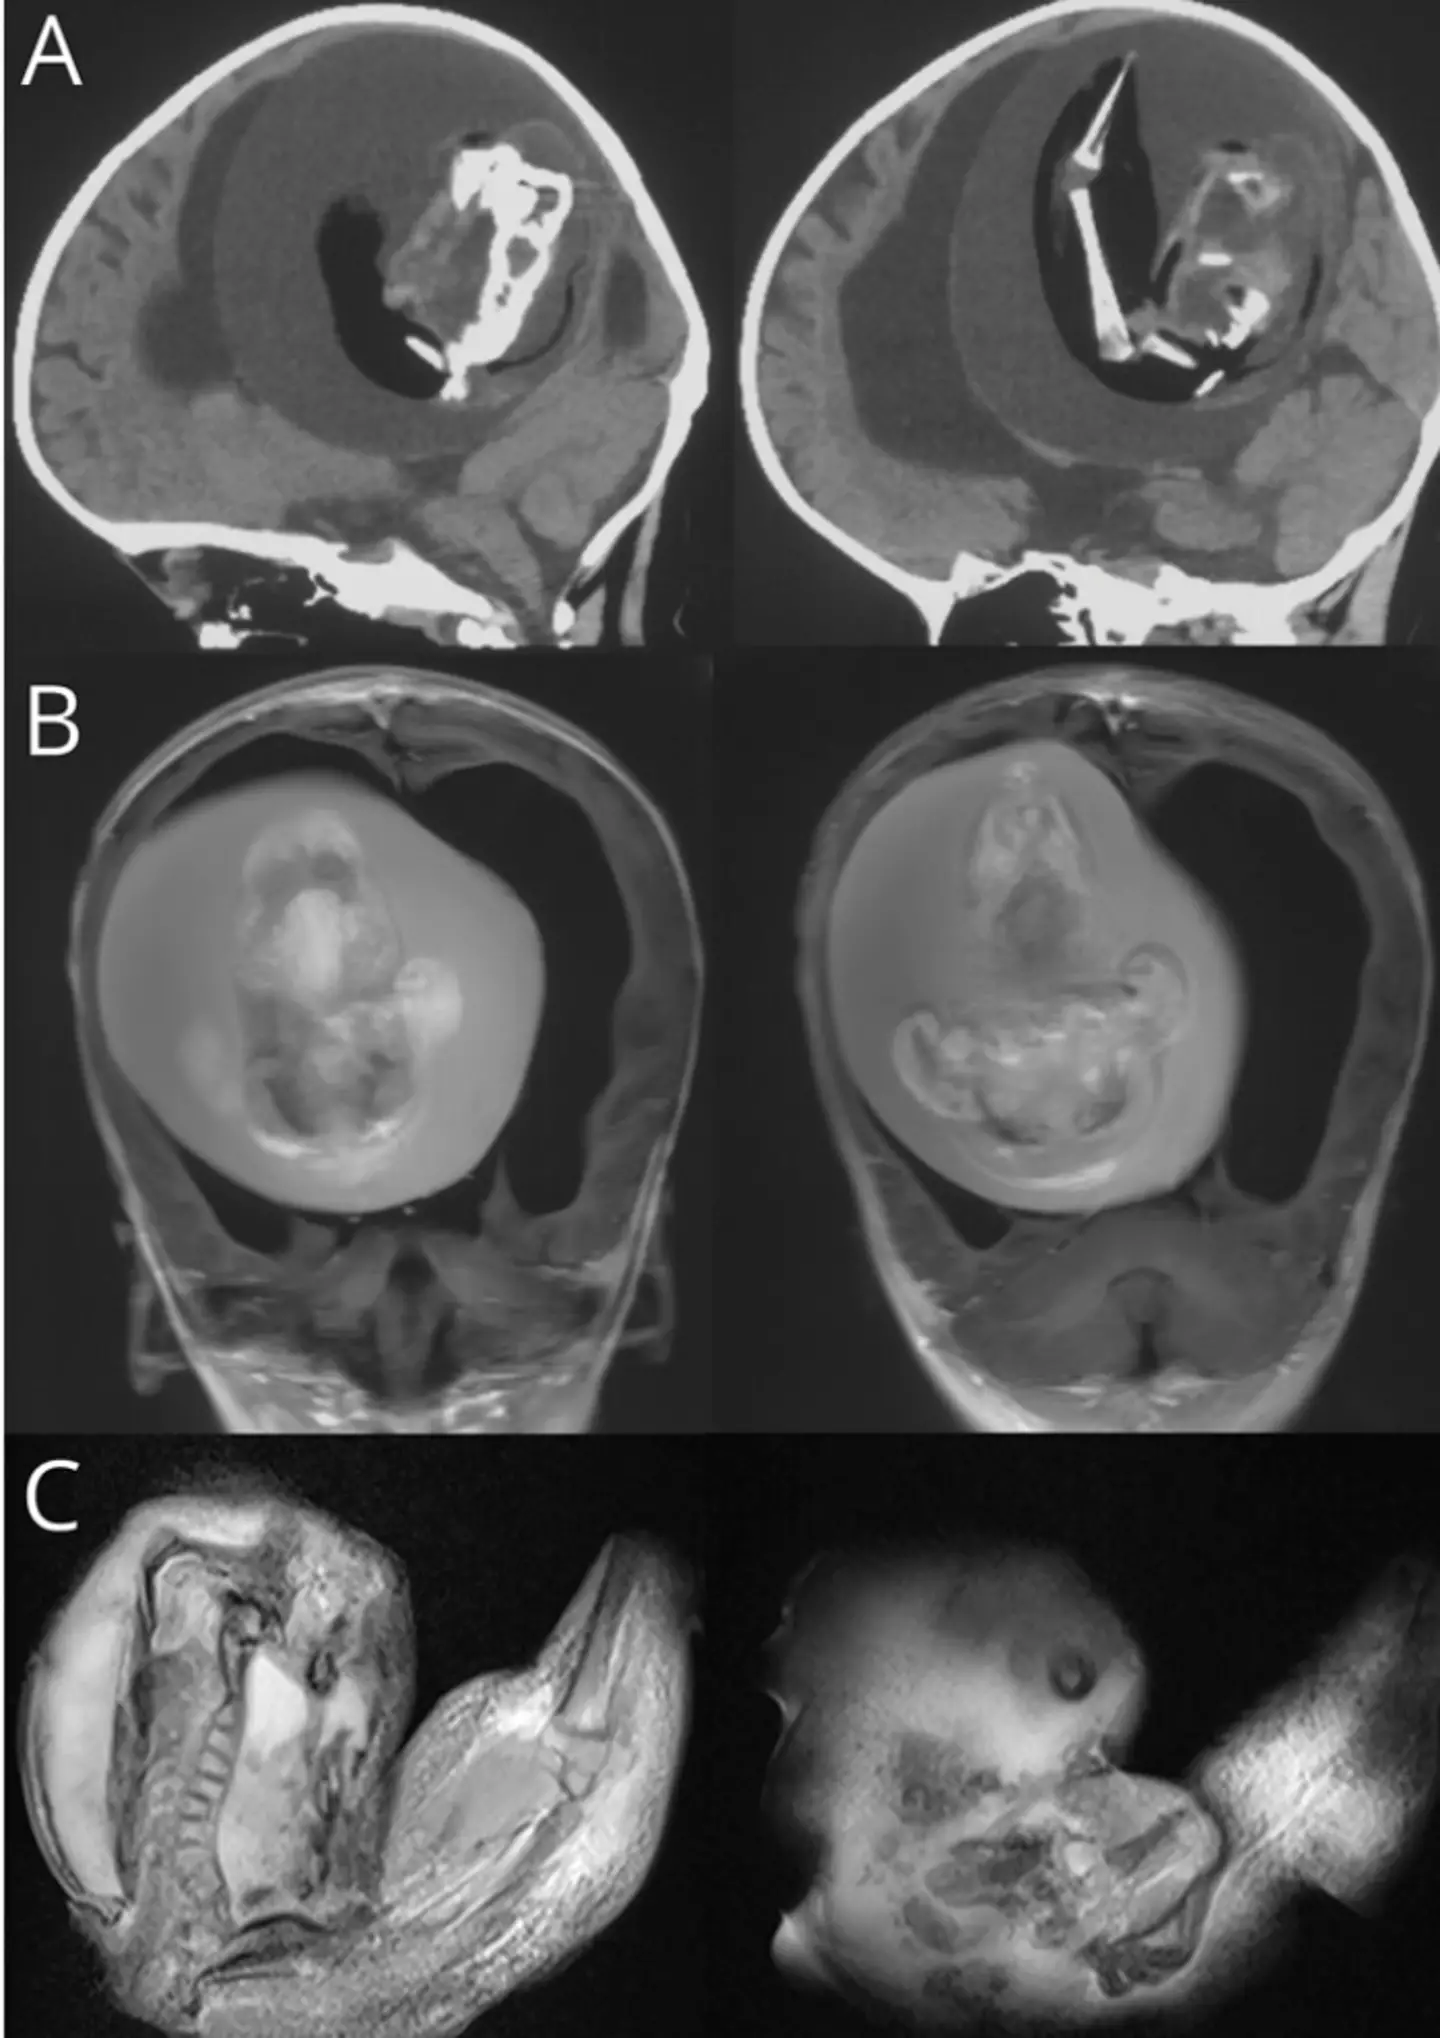

And after being taken in to see doctors in Shanghai, a head CT scan revealed a rare finding.

The study explains the scan revealed there was a 'large mass' in the young girl's cerebral hemisphere - the part of the brain that not only controls muscle function but also speech and learning.

The mass measured '13-cam maximum diameter' and had 'internal bone structure' with a 'smooth boundary'.

The study adds: "Both ventricles and third ventricle had hydrops, with a fetal shape at a continuous level, along with apparent compression near the cerebral parenchyma."

"Following complete mass resection, mouth, eye, arm, and hand shapes could be observed," the study adds.